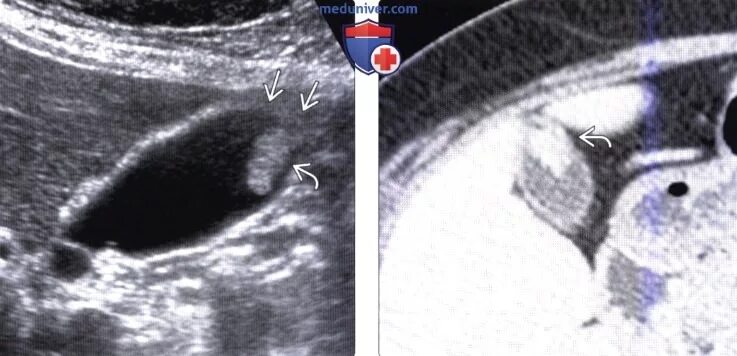

Полип желчного пузыря мкб 10 у взрослых